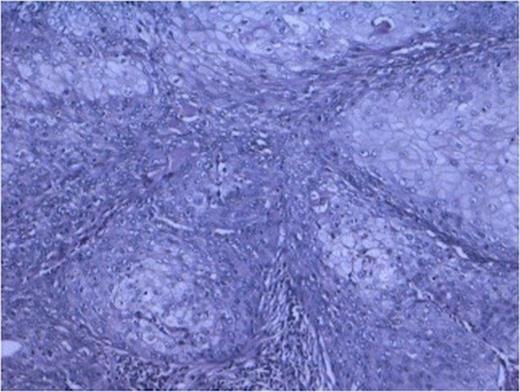

Tubules showing thyroidisation favouring chronic pylonephritis. (100x H and E stain).

The sections from various representative areas revealed dilated pelvicalyceal system lined by metaplastic squamous epithelium and shows changes of chronic pyelonephritis (Fig 2).